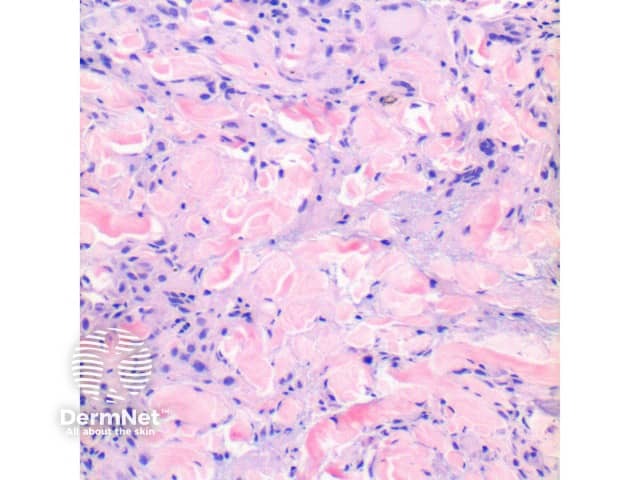

Figure 4